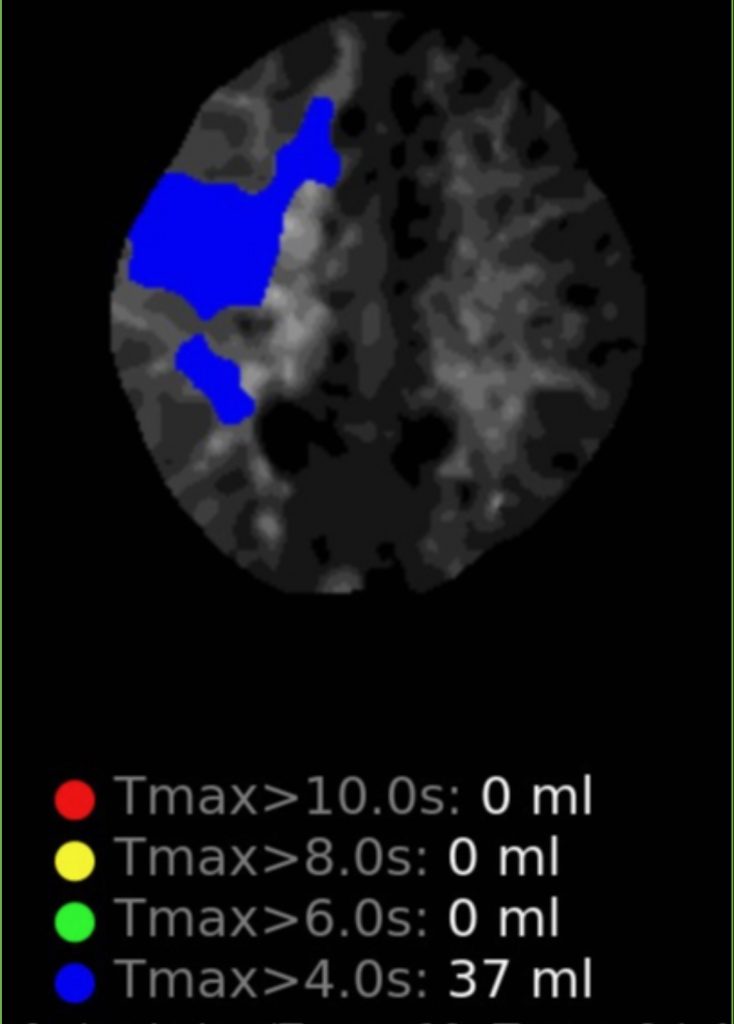

A right sided Encephaloduroarteriosynagios (EDAS) procedure was undertaken in which the right superficial temporal artery (STA) is sewn (synangiosed) to the pia in an effort to generate vascular arborization and increased blood flow to the hemisphere (Figure 3).